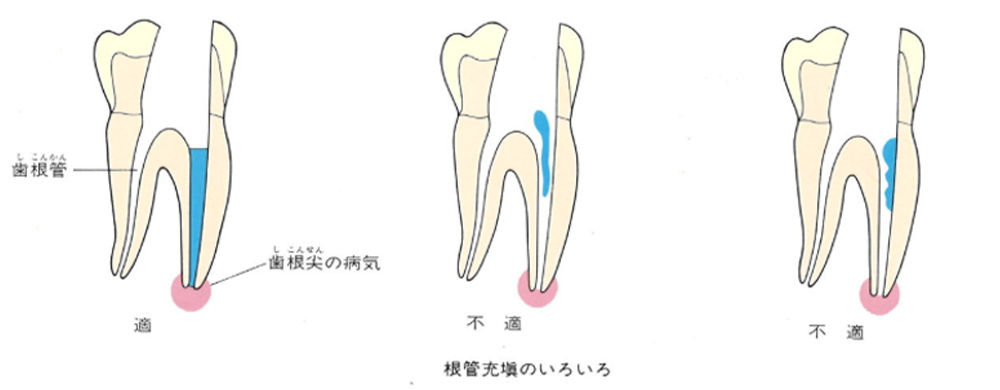

ガッタパーチャポイントは、理想的には歯根(シコン)の先ピッタリが良いと言われています。

しかし先ほど説明したように根管(コンカン)の形態は非常に複雑怪奇です。なので一概にピッタリが良いと限らないケースもあります。

ここでは一応、根尖(コンセン)付近が良いということにしておきましょう。

上の図にあるように神経の管に入れる薬が根尖(コンセン)まで入っていなかったり、途中までしか入っていなかったり、薬がスカスカだったりするとその空間にばい菌が繁殖して感染を起こします。

そうすると神経を取ったはずなのに、その後歯ぐきが腫れて痛くなるのです。

この根っこの病気を根尖性歯周炎というのです。そしてこの根尖性歯周炎を治すことを感染根管治療と言います。

大事な話なのでもう一度説明します。

①の写真はどちらかの歯医者さんで神経を取ってもらったレントゲン写真です。根っこの中に薬が全く入っていません。

②の模式図で青く描かれている部分が薬です。

根の先を見ると小豆ぐらいの大きさの黒い影が見えます。根の中でばい菌が繫殖し感染を起こすとこのような黒い影ができます。黒い影の部分は膿(ウミ)が貯まっています。こうなると腫れて痛みが出てくるのです。

③、④の写真はそれを治した後のレントゲン写真とその模式図です。白く映っている薬が根の先まできちんと入っているのが確認できます。そして根の先にあった黒い影が消えているのが分かります。根の先の炎症が治って、骨が再生すると白く映るのです。